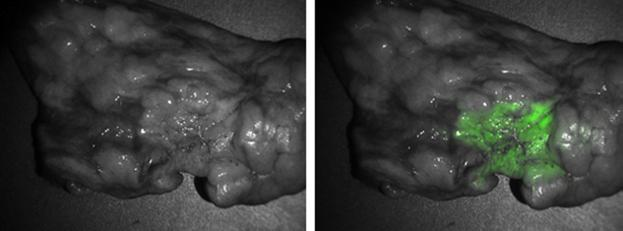

Upon opening the chest cavity, the primary lesion was located using traditional methods of visual inspection and manual palpation. The cancer was imaged and photodocumented with a fluorescence imaging system (Quest Medical Imaging's Artemis fluorescence imaging system) and the FloCam system developed in their laboratory.

In seven of the 50 cases (14%), the tumor could easily be identified by its fluorescence. The tumors ranged in size from 1.1 to 8.0 cm, but size did not influence fluorescence. All of these tumors were within 1.2 cm of the lung surface.

Of the remaining 43 tumors, 39 appeared fluorescent after the overlying tissue was opened and the tumor exposed. The fluorescence was uniform across the tumor's surface, and the demarcation between tumor and normal surrounding tissue was clearly visible. On average, the optical imaging was quick, ranging from five to 15 minutes.